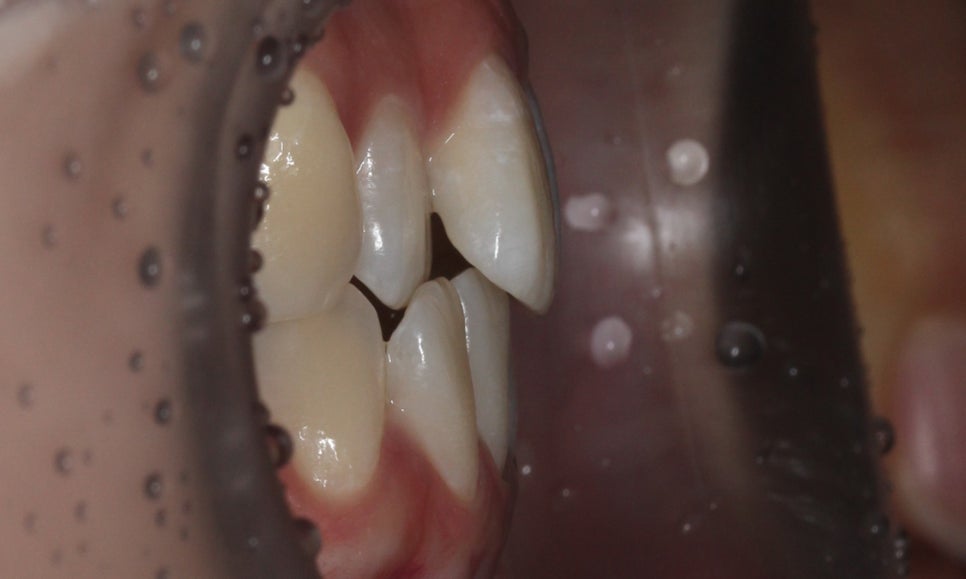

좌우의 교합평면을 보면 구치부의 교합은

크게 틀어진 부분 없이 양호한 상태인데요,

상악의 경우 송곳니의 위치나 각도도

좋기 때문에 부분교정도 가능하나

전체적인 교합을 바르게 하기 위해

자가결찰브라켓인 클리피씨교정 장치를

적용하여 전체교정을 진행하였습니다.

상악의 경우 설측으로 뻐드러져 있는

측절치의 바른 교정이 중요한 포인트이기 때문에

이를 중심으로 교정 계획을 수립하였습니다.

또한 미세하게 발견되고 있는 crowding으로 인해

삐뚤어진 정중선 역시 바른 각도로 교정하도록 하였습니다.

하악은 상악에 비해 심하게 틀어지진 않았지만

전치부의 치아들이 회전된 모습이 나타나기 때문에

이를 바르게 교정하여 전치부의 심미성을

보완하도록 하였습니다.